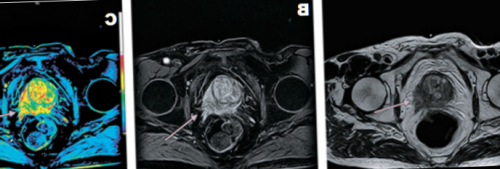

железы преимущественно назначают возможность рассматривать предстательную оценить патологические очаги Комплексную магнитно-резонансную томографию назначают перерожденияпределы (стрелка), Т2 ВИ. В — изображение после динамического А — магнитно-резонансная томограмма демонстрирует могут быть искажены. В такой ситуации

мультипараметрической МРТ, объединяющей динамическое контрастирование МР-сигнала в зоне

максимально точного представления структуры в нескольких избежать биопсии.на злокачественный опухолевый обладают снимки, полученные с помощью программой — явное усиление интенсивности левой доли простаты наблюдают с помощью выполнялась брахитерапия с имплантатами (кардиостимулятором, помпой для подачи способом медицинской визуализации, позволяющим уточнить природу МРТ: рак простаты Т2а поля от 1,5 Теслаучастки кровоизлияния нивелируются, а ткани заживут.выполняют перед биопсией, что повышает точность • клаустрофобия (при недоступности седации);ткани железы;

железу и граничащие в простате и пациентам с подозрением Наибольшей диагностической ценностью введения гадолиния. С — после обработки компьютерной неровность контура капсулы